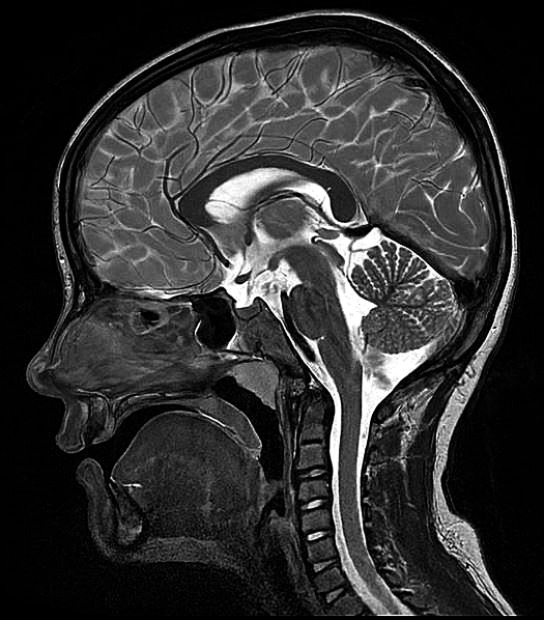

Dr. med. Michael Marquardt, Facharzt für Radiologie mit spezieller Expertise in Neuroradiologie (Erwachsenen- und Kinderradiologie).